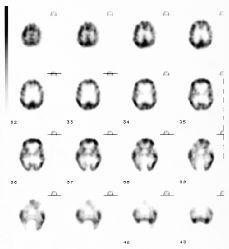

SPECT cerebral con 99mTc-HMPAO en una paciente diagnosticada de megacisterna magna

Fernández, Mora, Ricart , Castell, Benítez, Muñoz, Martín-Comín

Rev Esp Med Nucl Imagen Mol 1999;18:110